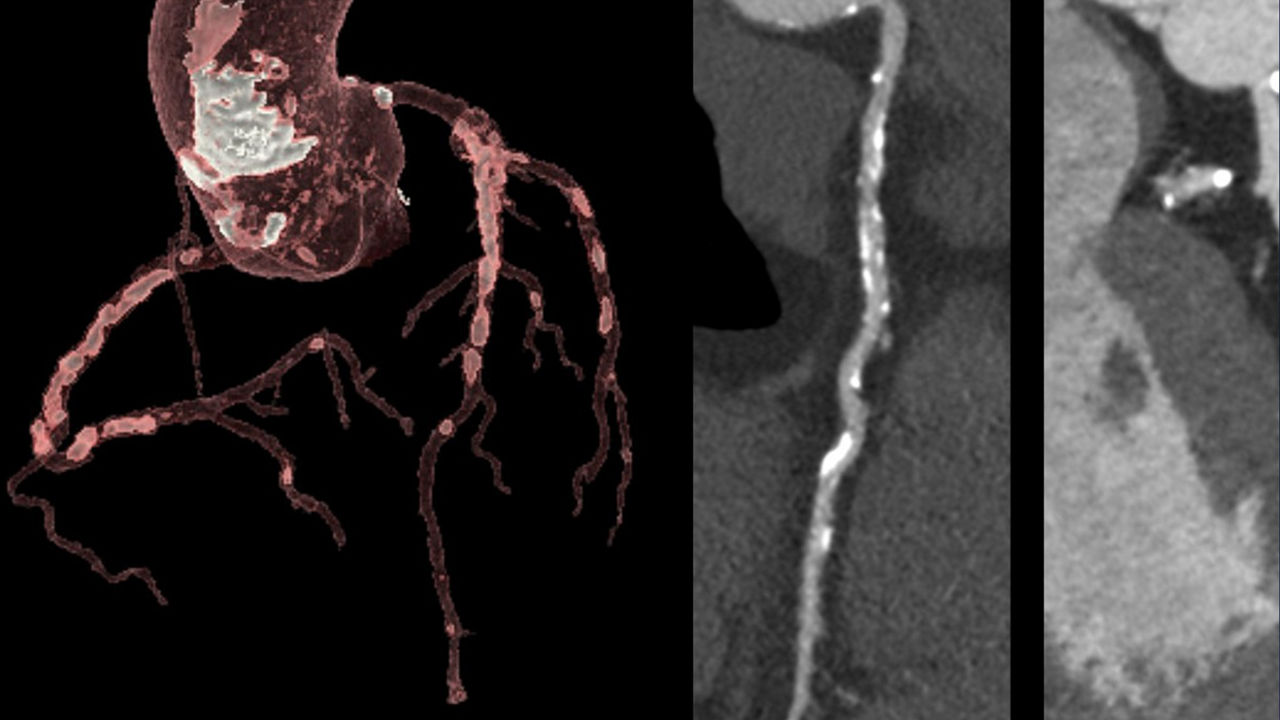

Leveraging transformational imaging technology to realize the promise of precision medicine and help deliver better outcomes. Our medical imaging products range from systems, including MRI, CT, PET, SPECT, Ultrasound, Mammography and X-ray, to digital and AI solutions to help drive healthcare digitialization, help enable faster exam workflow, improve clinical outcomes and increase efficiencies.